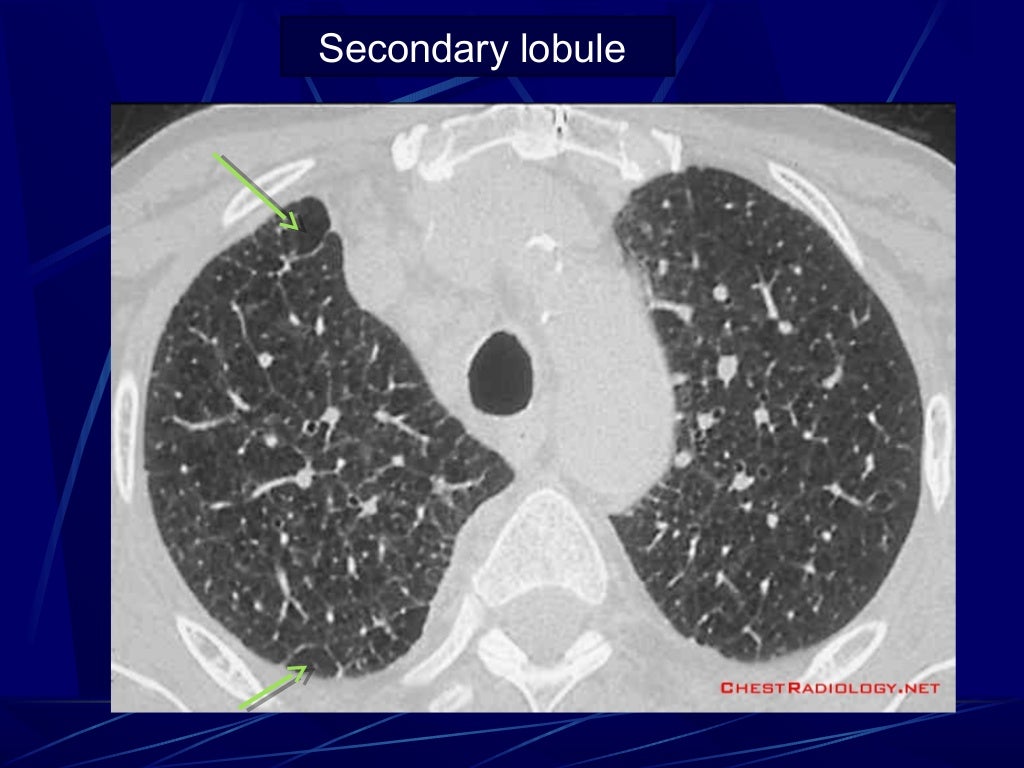

HRCT Reticular pattern